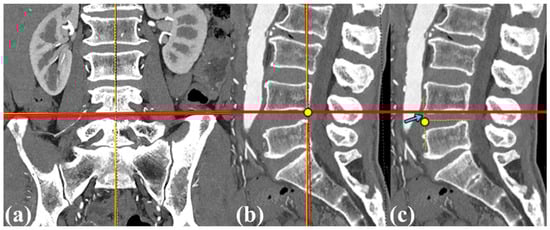

The iliac crest height was also quantitatively assessed on coronal and sagittal CT images using the Picture Archiving and Communication System (PetaVision for Clinics, 3.1; Korea University Anam Hospital, Seoul, Republic of Korea). The assessment process first defined a tangential line touching both iliac crests in the coronal plane (Figure 2a). The red line serves as a reference for subsequent measurements. In Figure 2b,c, the minimum distance between this tangential line and the reference point in the L4–5 disc space was measured (sky blue arrow). To minimize potential rotational errors caused by the patient lying obliquely on the CT table, an axis passing through the ventral edge of the L4–5 disc space was established in the sagittal plane. This axis touches both iliac crests cranially and tangentially. The shortest distance from this line to the center of the ventral edge of the L4–5 disc space was evaluated as the iliac crest height relative to the L4–5 disc space. Additionally, CT scans were used to assess the presence of disc pathology, including the vacuum phenomenon and endplate sclerosis, and to measure both anterior and posterior disc heights.

Figure 2. Measurement of the distance of the iliac crest in relation to the L4–5 disc space by computed tomography (CT). (a) The thick red line represents the connection between the highest points of both iliac crests in the CT coronal plane, with the midpoint of this line serving as a reference. (b) In the sagittal plane, the midpoint of the coronal plane’s red line is indicated by a yellow dot, which is then projected to create a horizontal red line. (c) The distance between the yellow dot marking the ventral side midpoint of the L4–5 disc space and the horizontal red line is measured as the distance between the iliac crest and the L4–5 disc space (light blue arrow).